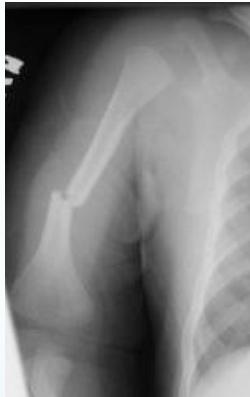

- Femur shaft fracture

- <1 year of age (70%)

- Transverse fracture

- Humeral shaft fracture

- <3 years of age